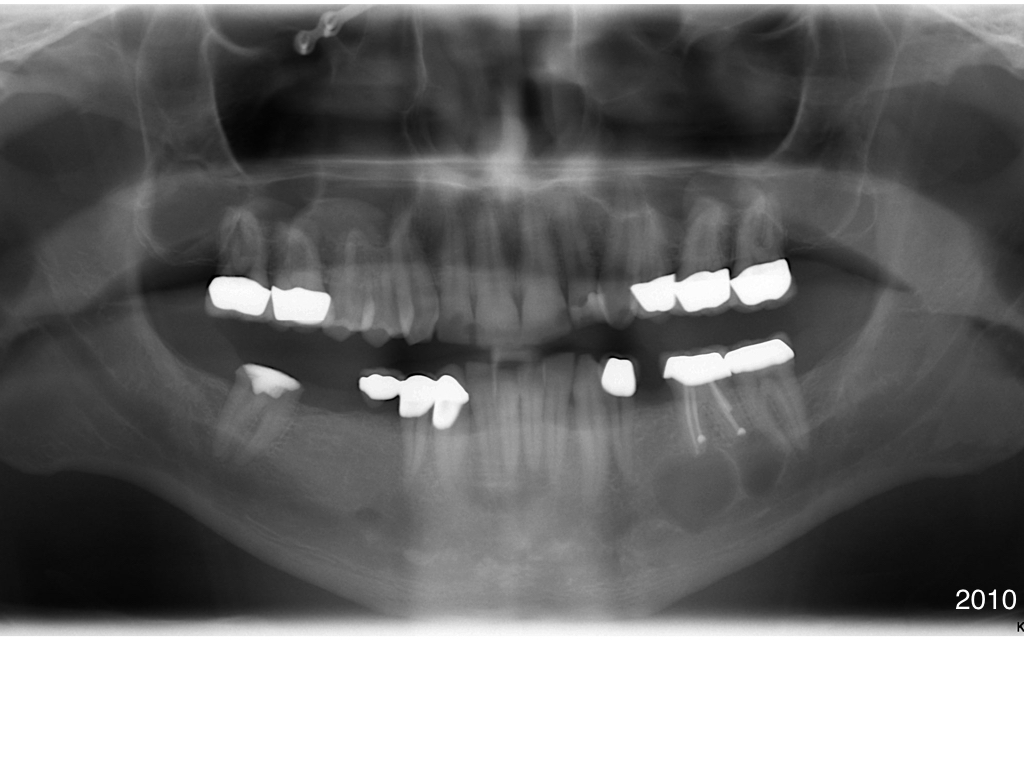

Ohne Alternative steht für mich die Extraktion von 36. Selbst bei (kombiniert) chirurgischer Therapie würde ich selbst sowas nicht im Mund haben wollen. So hätte ich es der Kollegin auch nahe gebracht. Gruß. Kommentiere ↓